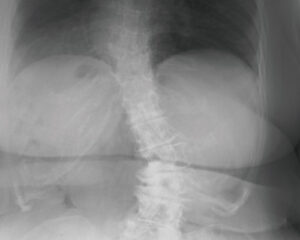

椎間板の変性段階(D1~D6)

D6 15年以上経過

椎間板の変性が慢性化した最終ステージで、サブラクセーションが15年以上放置されている状態になります。椎間板の水分は放出され、椎間板スペースはほぼ消失、骨が自然癒合を起こし可動性が著しく減少してしまいます。上下の椎骨が更に接近し可動性が更に制限され、神経への負荷を避けるための防御反応により、カルシウムが沈着し更に補強を始めます。ケアをしても椎間板スペースや骨の変形には変化が見られませんが、神経機能が改善することは可能です。